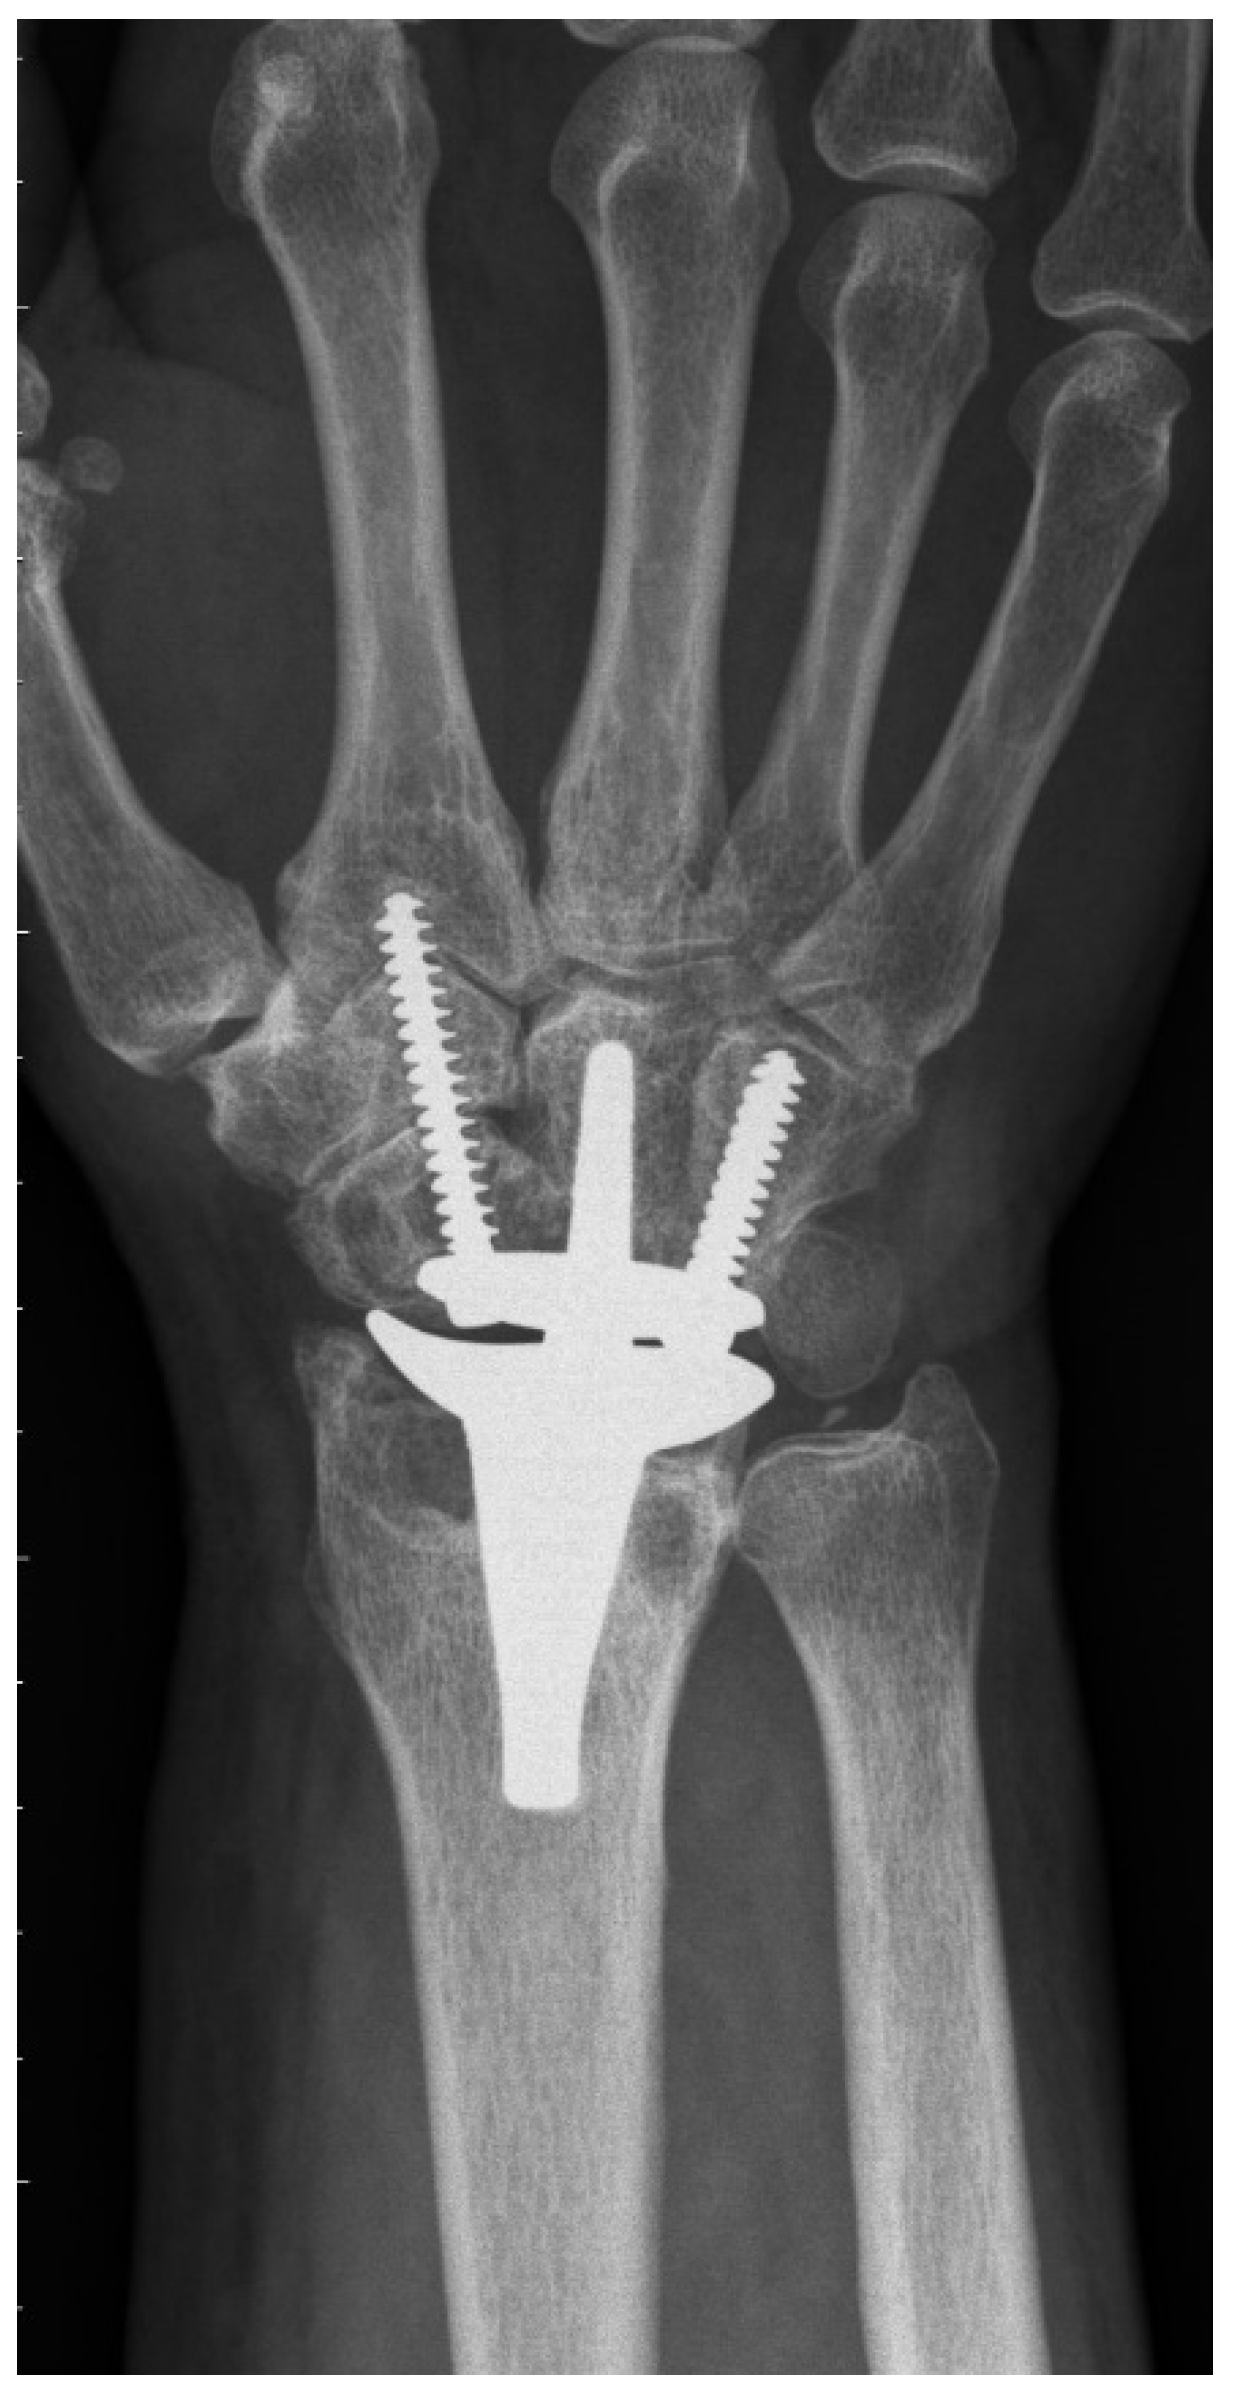

Figure 2. Final radiograph (72 months postoperatively) of a CCR cohort patient with massive radial impaction syndrome.

The CRR group showed 17 complications in 15 wrists. The most common one was radial impaction (n = 10) (Figure 2), leading to four re-operations including scaphoidectomy. Moreover, we could detect two ganglions, one complex regional pain syndrome, and one postoperative surgical site infection, which could successfully be treated with antibiotics. One patient received De Quervain’s tenosynovitis release. One patient presented with continuous pain in the region of the hamate with simultaneous radiolucency around the ulnar screw. During revision surgery, the loose ulnar screw was exchanged to a longer one. Another patient developed massive pain due to radial screw breakage, which was treated by exchanging the broken screw. Radiological abnormalities were observed in 19 patients: radial radiolucency (n = 19), carpal radiolucency (n = 14), and screw breakage (n = 1).

To the best of our knowledge, PRC has never been previously described for primary TWA implantation in the current literature (see Table 5 for a summary of the literature). Gupta merely described, in his original surgical technique for ReMotion prosthesis, a salvage procedure for failed PRC or failed 4-corner fusions using TWA [1]. Interestingly, he recommended harvesting the pisiform for reconstruction of the missing distal pole of the scaphoid, where the radial screw is consecutively inserted. The present study shows that this additional step is not necessary, because fixation of the radial screw in the trapezoid and second metacarpal is sufficient for applying slight compression and rotational stability to the carpal prosthesis. Conney et al. [9] are the only authors who reported details on their carpal resection technique (i.e., the manufacturer’s recommended technique). Interestingly, we also found in the manufacturer’s operative technique that the producer recommends a more distal resection in patients with excessive carpal erosion or advanced degenerative joint disease [10]. However, we assume that this adaption would probably also not prevent TWA patients from being prone to suffering from radial impaction syndrome. This predominant clinical complication in the CCR group is most probably caused by the remaining distal pole of the scaphoid. Radiographically, this issue can be perfectly illustrated: Figure 2 shows a dorsopalmar radiograph of the wrist in neutral position with respect to radial and ulnar deviation (the third metacarpal and the long axis of the metacarpal are perfectly aligned). Even in this neutral position—without actively radially deviating the carpus—one can see contact or impingement between the prosthesis’s radial socket and the distal pole of the scaphoid. This situation led to four reoperations including resection of the distal pole of the scaphoid, which completely resolved the patient’s complaints. This further confirms the hypothesis of a correlation between the CCR technique and radial impaction syndrome. Moreover, we suppose that this complication is due to particular challenges associated with TWA. Inspecting the postoperative radiograph in Figure 1a, due to a sufficient distance between the socket and the scaphoid, the before-mentioned issue of radial impaction syndrome would be difficult to comprehend or predict. Despite intraoperative visual and fluoroscopic evaluation for any impingement in every extreme position while performing the CCR technique, radial impaction syndrome seems to develop in the postoperative course. One of the main reasons might be that TWA is very prone to periprosthetic, osseous remodeling. Osteophytes and osteolysis might cause or aggravate the morphologic correlate of radial impaction syndrome, which can be seen in Figure 2. This 6-year postoperative radiograph was taken from the same patient as in Figure 1a. The phenomenon has already been observed by Boeckstyns and Herzberg [11], who discuss possible reasons for osseous reactions in TWA. This publication mainly focused on radiolucency, which also represented a clinically asymptomatic, radiographic abnormality in both our cohorts.